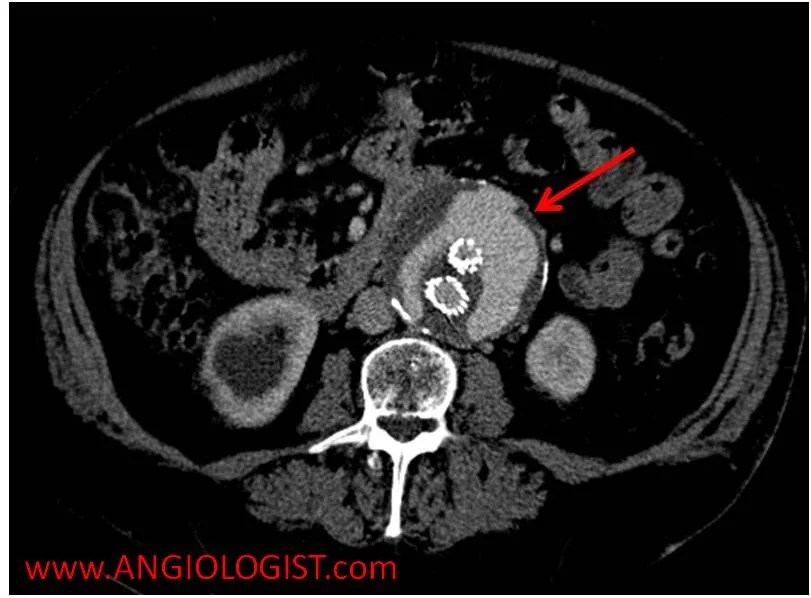

Endoleak an endoleak is the leaking of blood outside a stent graft and within an aneurysm sac By grasping the nuances of these types, individuals and healthcare professionals can better comprehend the condition and make informed decisions about its management.

It’s a common complication of endovascular aneurysm repair (evar) Causes & management firstly, let’s understand the classification system used to categorize endoleak types There are five types of an endoleak

Endoleaks may require endovascular treatment methods to prevent aneurysm rupture. Open surgery is an alternative for individuals who cannot be treated successfully with less invasive techniques Type iv endoleak a type iv endoleak often resolves on its own, once blood clotting has normalized. An endoleak is a leak of blood into the aneurysm sac after an endovascular aneurysm repair (evar) procedure

Learn about the five types of endoleaks, how they are diagnosed and treated, and why they can be dangerous. An endoleak is a complication of endovascular aneurysm repair (evar) where blood leaks into the aneurysm sac, increasing the risk of rupture Learn about the various types and how they are diagnosed and skillfully treated at tampa general hospital. Endoleaks are characterized by persistent blood flow within the aneurysm sac following endovascular aneurysm repair (evar)

The management of endoleaks remains an inherent challenge to endovascular aneurysm repair (evar), particularly as evolving techniques and devices have allowed treatment of increasingly complex aneurysm anatomy